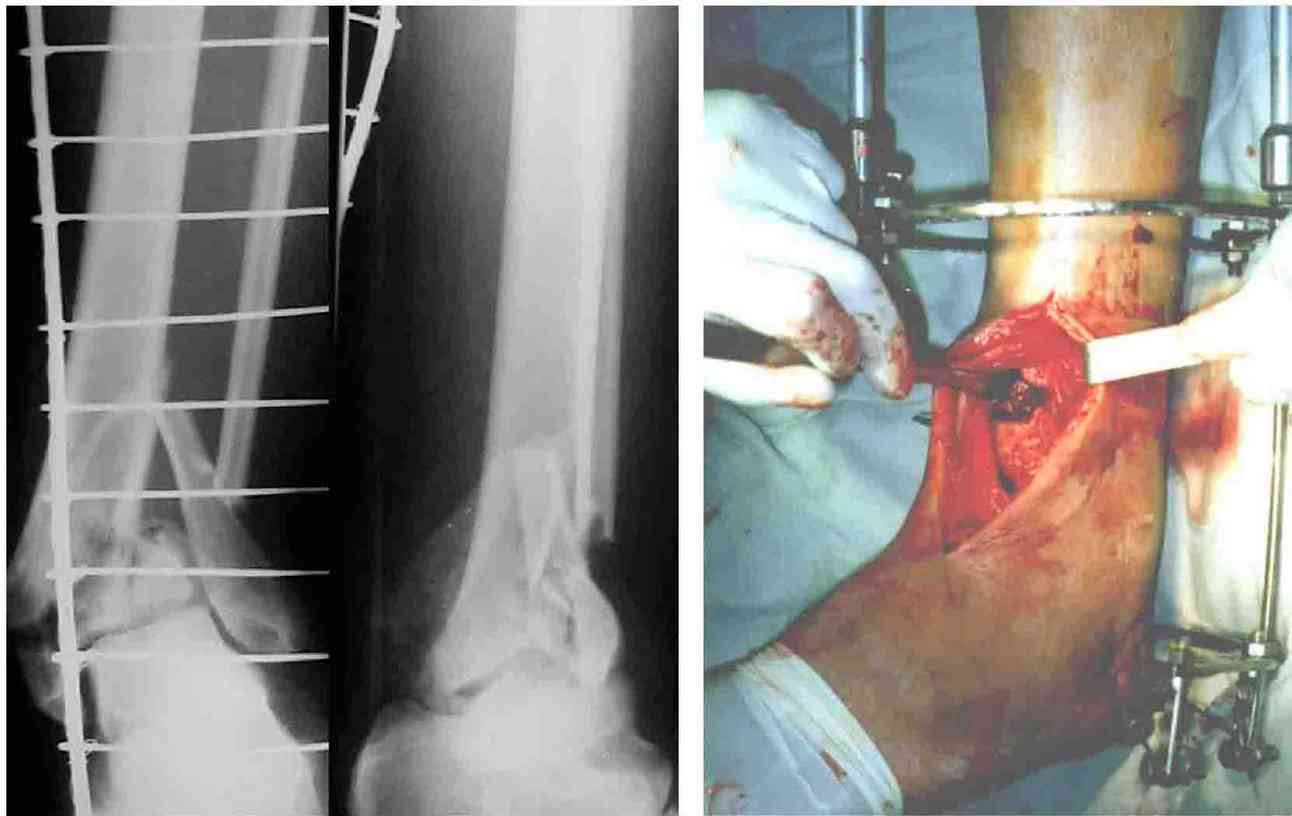

Во вложении - картинки из моей книжки как раз по этой теме

Схемы коррекции различных видов смещения в аппарате

Коррекция длины

Коррекция ротации

Коррекция ширины

В следующих письмах - дополнительные иллюстрации

Открытая репозиция.

Ничто особо не мешает, наоборот - все видно, требования к фиксации не очень высоки - можно просто фиксировать спицей или винтомю Внешний аппарат берет основную нагрузку

Пример -

задний край и диафиз

По поводу конкретного вопрошаемого случая:

1. Скорее всего в аппарате удасться вывести закрыто всё, кроме внутренней лодыжки. Открывайтесь и фиксируйте либо спицей с упором,

либо винтом.

2. ЭОП - очень спорное достижение в таких случаях. Сильные искажения.

Буквально вчера переделывали практически похожий случай. На ЭОПе всё идеально. На пленке - ступенька переднего края. Брали повторно, но уже

пригласили рентгенлаборантку в операционую сделать снимок.

3. Последнее время всё чаще делаем аппарат Илизарова в симбиозе с винтами, которыми фиксируем края (передний и задний), лодыжки и теперь - диафиз.

Позволяет пораньше снять аппарат.

На фото простой суставной, метафиз. оскольчатый с переходом на диафиз перелом, пластина MIPO.